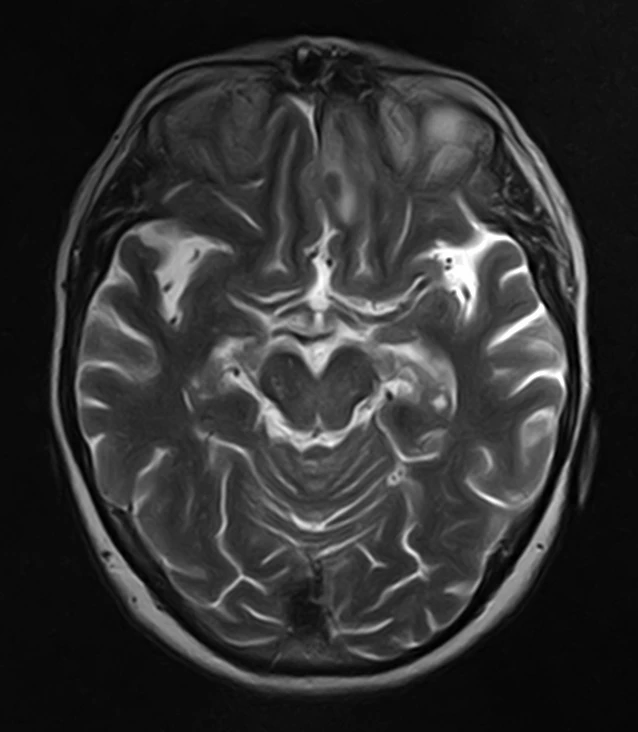

Женщина 32 года. Больной считает себя с 2024 г, когда стала отмечать онемение угла рта. Со слов пациентки ей был предварительно выставлен диагноз - РС, но дополнительных методов обследования и специфического лечения не проводилось. В настоящее время жалоб нет. В исследовании от октября 2024 отмечался очаг в левой затылочной доле с выраженным контрастированием, в настоящее время этот же очаг отмечается с сохраняющимся контрастированием. Формально - есть выполнение критериев диссеминации и в пространстве (юкстакортикальный и перивентрикулярный очаги есть), и во времени (есть усиливающиеся и неусиливающиеся очаги), клиника тоже вполне укладывается. Но! Найти в литературе подобных случаев мне не удалось, видел сам и максимум, что находил в литературе - полгода контрастирования. Получается, мы имеем дело с крайне атипичным рассеянным склерозом, или это не рассеянный склероз. А тогда что? Сосудистая мальформация не вариант - на SWI не видать. Какая-то ганглиоглиома? А другие очаги тогда что? Есть соображения? Кстати, диффузия стойко повышенная, и на б1000 почти не видно (изо). На Т2 не меняется